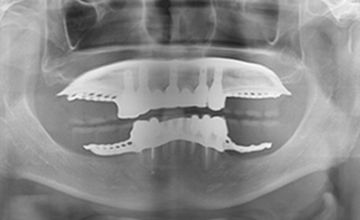

여러 개의 임플란트를 심은 뒤, 그 사이를 금속 막대로 연결해 튼튼한 지지대를

만들고, 그 위에 틀니를 안정적으로 고정하는 방식입니다.